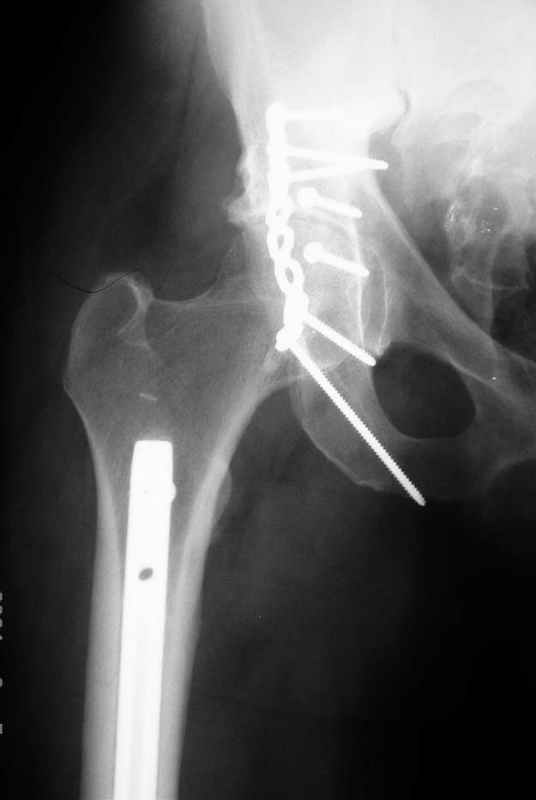

Не дождавшись советов, в понедельник прооперировал больного, заняло времени..., но все сделал в один этап: сначала фиксировал ипсилатеральный перелом бедра и шейки реконструктивным гвоздем Smith&Nephews, потом из расширенного илеофеморального доступа фиксировал перелом крыла подвздошной кости тягловым винтом, нейтрализующей пластиной заднюю колонну, и тягловыми винтами 3,5 мм переднюю колонну.

Несмотря на расширенный доступ, особой кровопотери не было, перелил только одну дозу эр.массы и на утро Нв- 10.5 и как ни странно больной не жалуется на сильные боли и стопа не *висит*, хотя при интраоперационной ревизии седалищного нерва обширная гематома в периневральной оболочке.

перелом крыла правой подвздошной кости, перелом обеих колонн вертлужной впадины, двусторонний перелом лонных костей (С2.2) повреждение передних связок правого крестцово-подвздошного сочленения,

ипсилатеральный перелом шейки и диафиза бедра.

К сожалению, набора для ретроградного или антеградного реконструктивного штифтования в операционной нет, поэтому доставка заняла н-ное время. Вопрос, который возник у меня- по поводу оптимальной тактики хирургии: вся фиксация в один этап из расширенного доступа или последовательно сначала бедро и позже реконструкция впадины, комбинированный доступ к впадине отдельно к передней и задней колоннам или из расширенного илеофеморального одного доступа. Все-таки решил остановиться на одноэтапном подходе и спустя 5 дней (как раз и наборы привезли) из расширенного илеофеморального доступа сначала фиксировал реконструктивным штифтом Smith&Nephews бедро и

шейку (благо перелом шейки 2 типа -относительно стабильный) затем фрагмент крыла подвздошной кости Lag screw, далее пластина на заднюю колонну и винты в переднюю колонну.(с размерами и направлением винтов ошибка вышла:-((, но интраоперационно у меня была полная уверенность , что винты *ушли* в лонную кость).

Еще раз спасибо за комментарии и готовность помочь с имплантами. Постоп картинки в приложении,